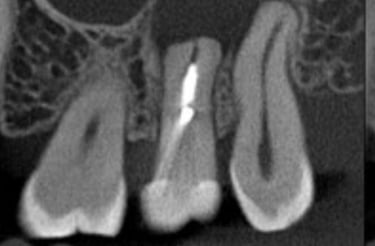

Aspecto Tomográfico Final do Enxerto e Planejamento Digital para o Implante

O enxerto de biomateriais possibilita a colocação de implantes mesmo em pacientes com pouco osso na região posterior da maxila, garantindo suporte seguro e duradouro para reabilitações

A cirurgia guiada utiliza planejamento digital e guias cirúrgicos impressos em 3D, oferecendo maior precisão, menor tempo de cirurgia e recuperação mais confortável.